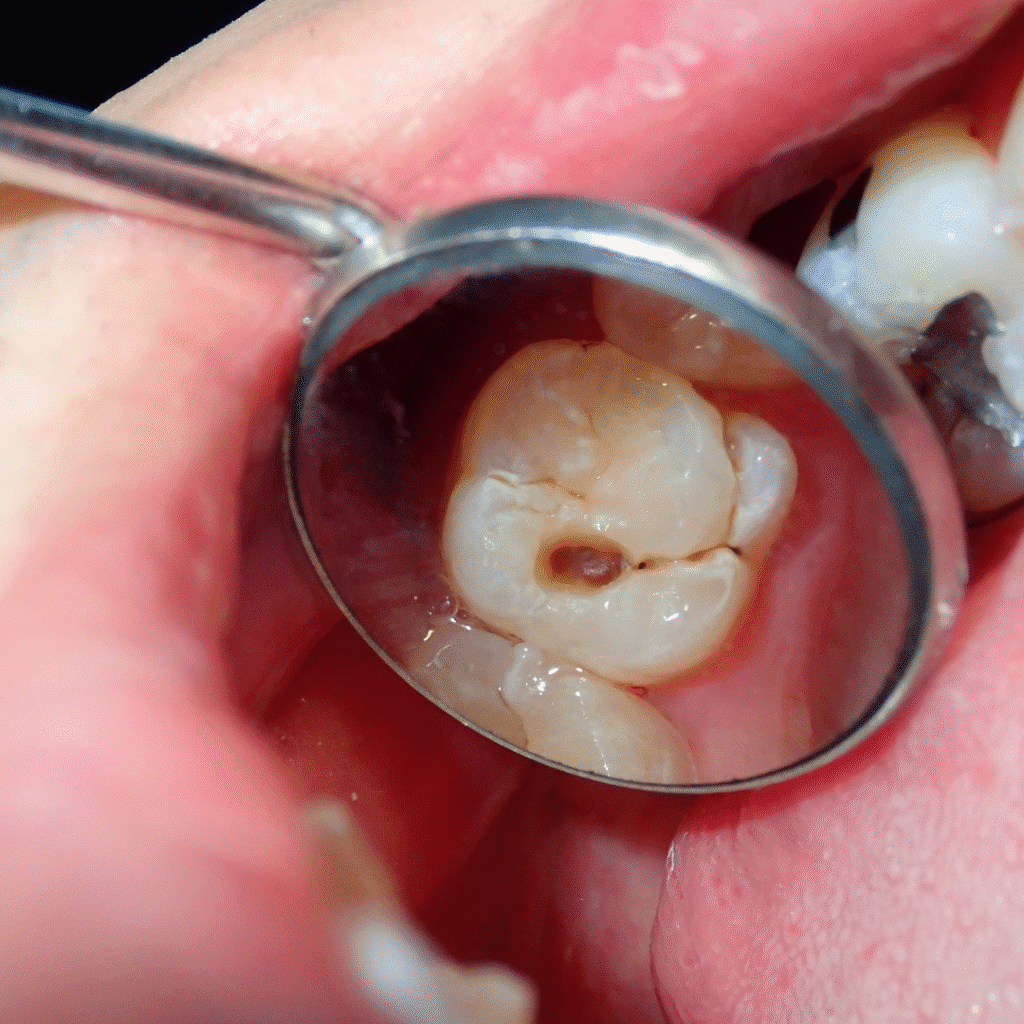

4. Deep grooves or pits in teeth

Molars with deep chewing surfaces can trap food and bacteria, making them more prone to cavities.

Cavities don’t usually cause pain until they reach deeper layers of the tooth — that’s why regular dental exams are so important.

• White or brown spots on the enamel

If decay progresses, you may experience visible holes, persistent toothache, or swelling near the gum line.